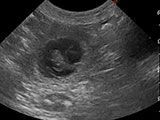

Für die letzte Belegung mit Iusha vom Hersberg haben wir uns nochmals für den kräftigen Deckrüden Sämi von der Balmfluh entschieden. Iusha hat 2 Rüden geworfen.

Iusha vom Hersberg